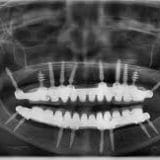

Revolutionize your dental journey with Dr. Rohit Yadav’s expertise. Unleash the potential of your smile today! When it comes to dental care, finding the right dentist is crucial. In India, there are numerous highly skilled dentists who specialize in various dental procedures, including dental implants and cosmetic dentistry. One such renowned dental professional is Dr....